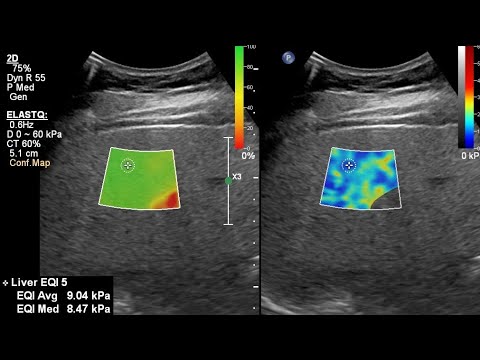

FibroScan, or elastography for liver stiffness, fibrosis, method, analysis